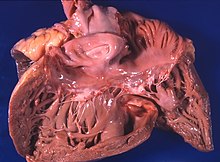

Cor pulmonale